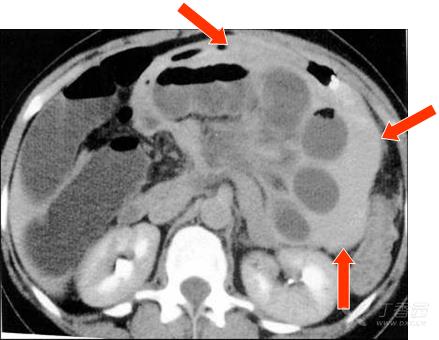

網膜孔疝的CT表現:網膜囊內見朝向網膜孔的鳥嘴狀充液氣腸管積聚,絞窄時有腹液; –腸系膜血管拉直、進入,胃受壓前移; –若盲、升結腸疝入,則右腹外側區不再顯示; –與左側十二指腸旁疝鑒別 ,前者疝入點相對較高,位肝門后方。

首次檢查圖像 1小時后復查,疝囊內腸管擴張明顯,囊內積血(紅箭),CT值高,示缺血嚴重。